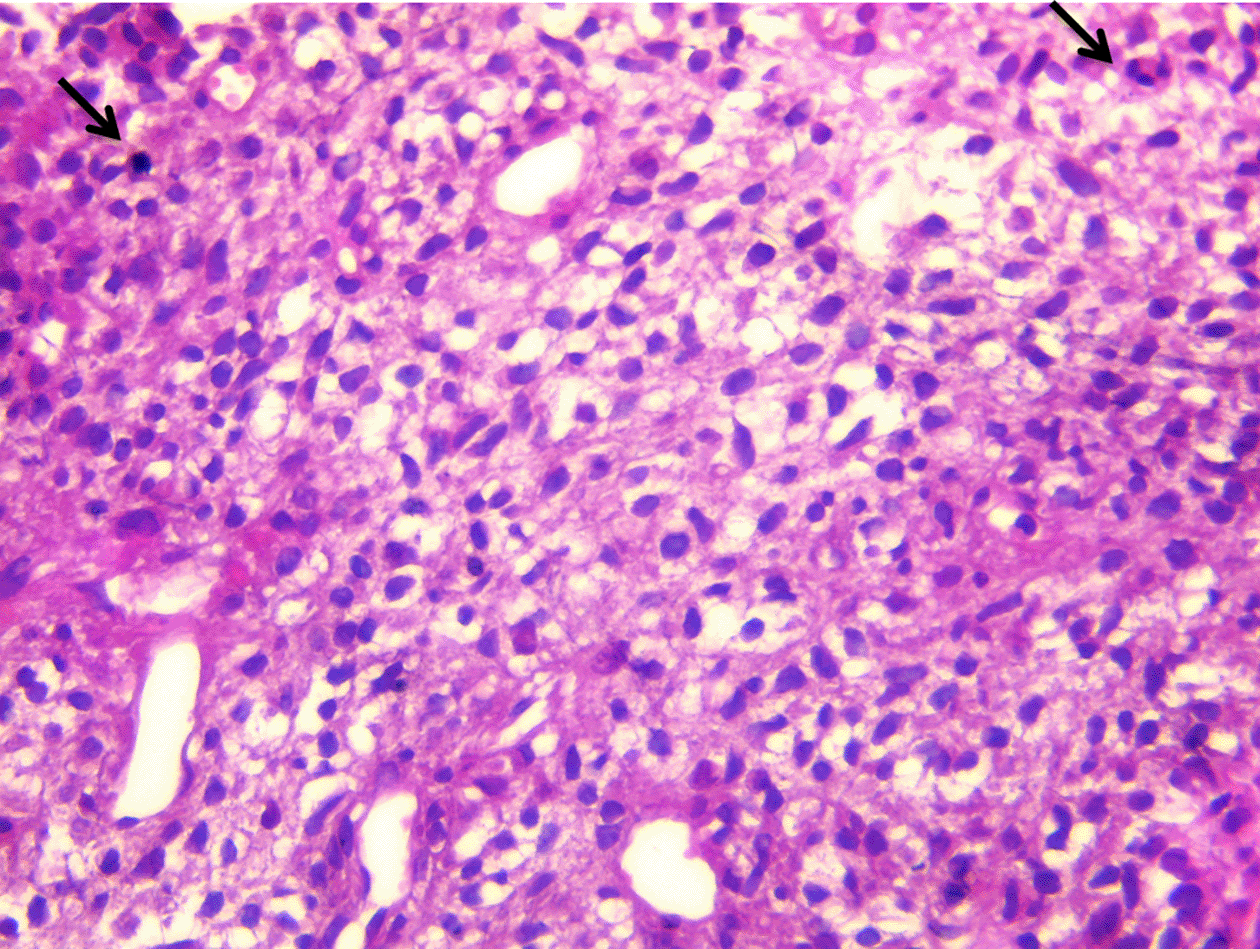

The Cardiac magnetic resonance imaging (MRI) results showed low signal on T1-weighted imaging and high signal on T2-weighted imaging of the mediastino-pulmonary mass (Figure 4). The patient accepted to undergo an urgent mass resection surgery to avoid total mitral valve obstruction and sudden death. The histological study of the resected mass confirmed the metastatic spread of malignant PTs to LA (Figure 5). The patient was discharged from the hospital after having an echocardiographic check-up, which demonstrated no residual tumor. However, three months after the surgery, she died from a huge relapse of mediastinal mass with tracheal invasion.